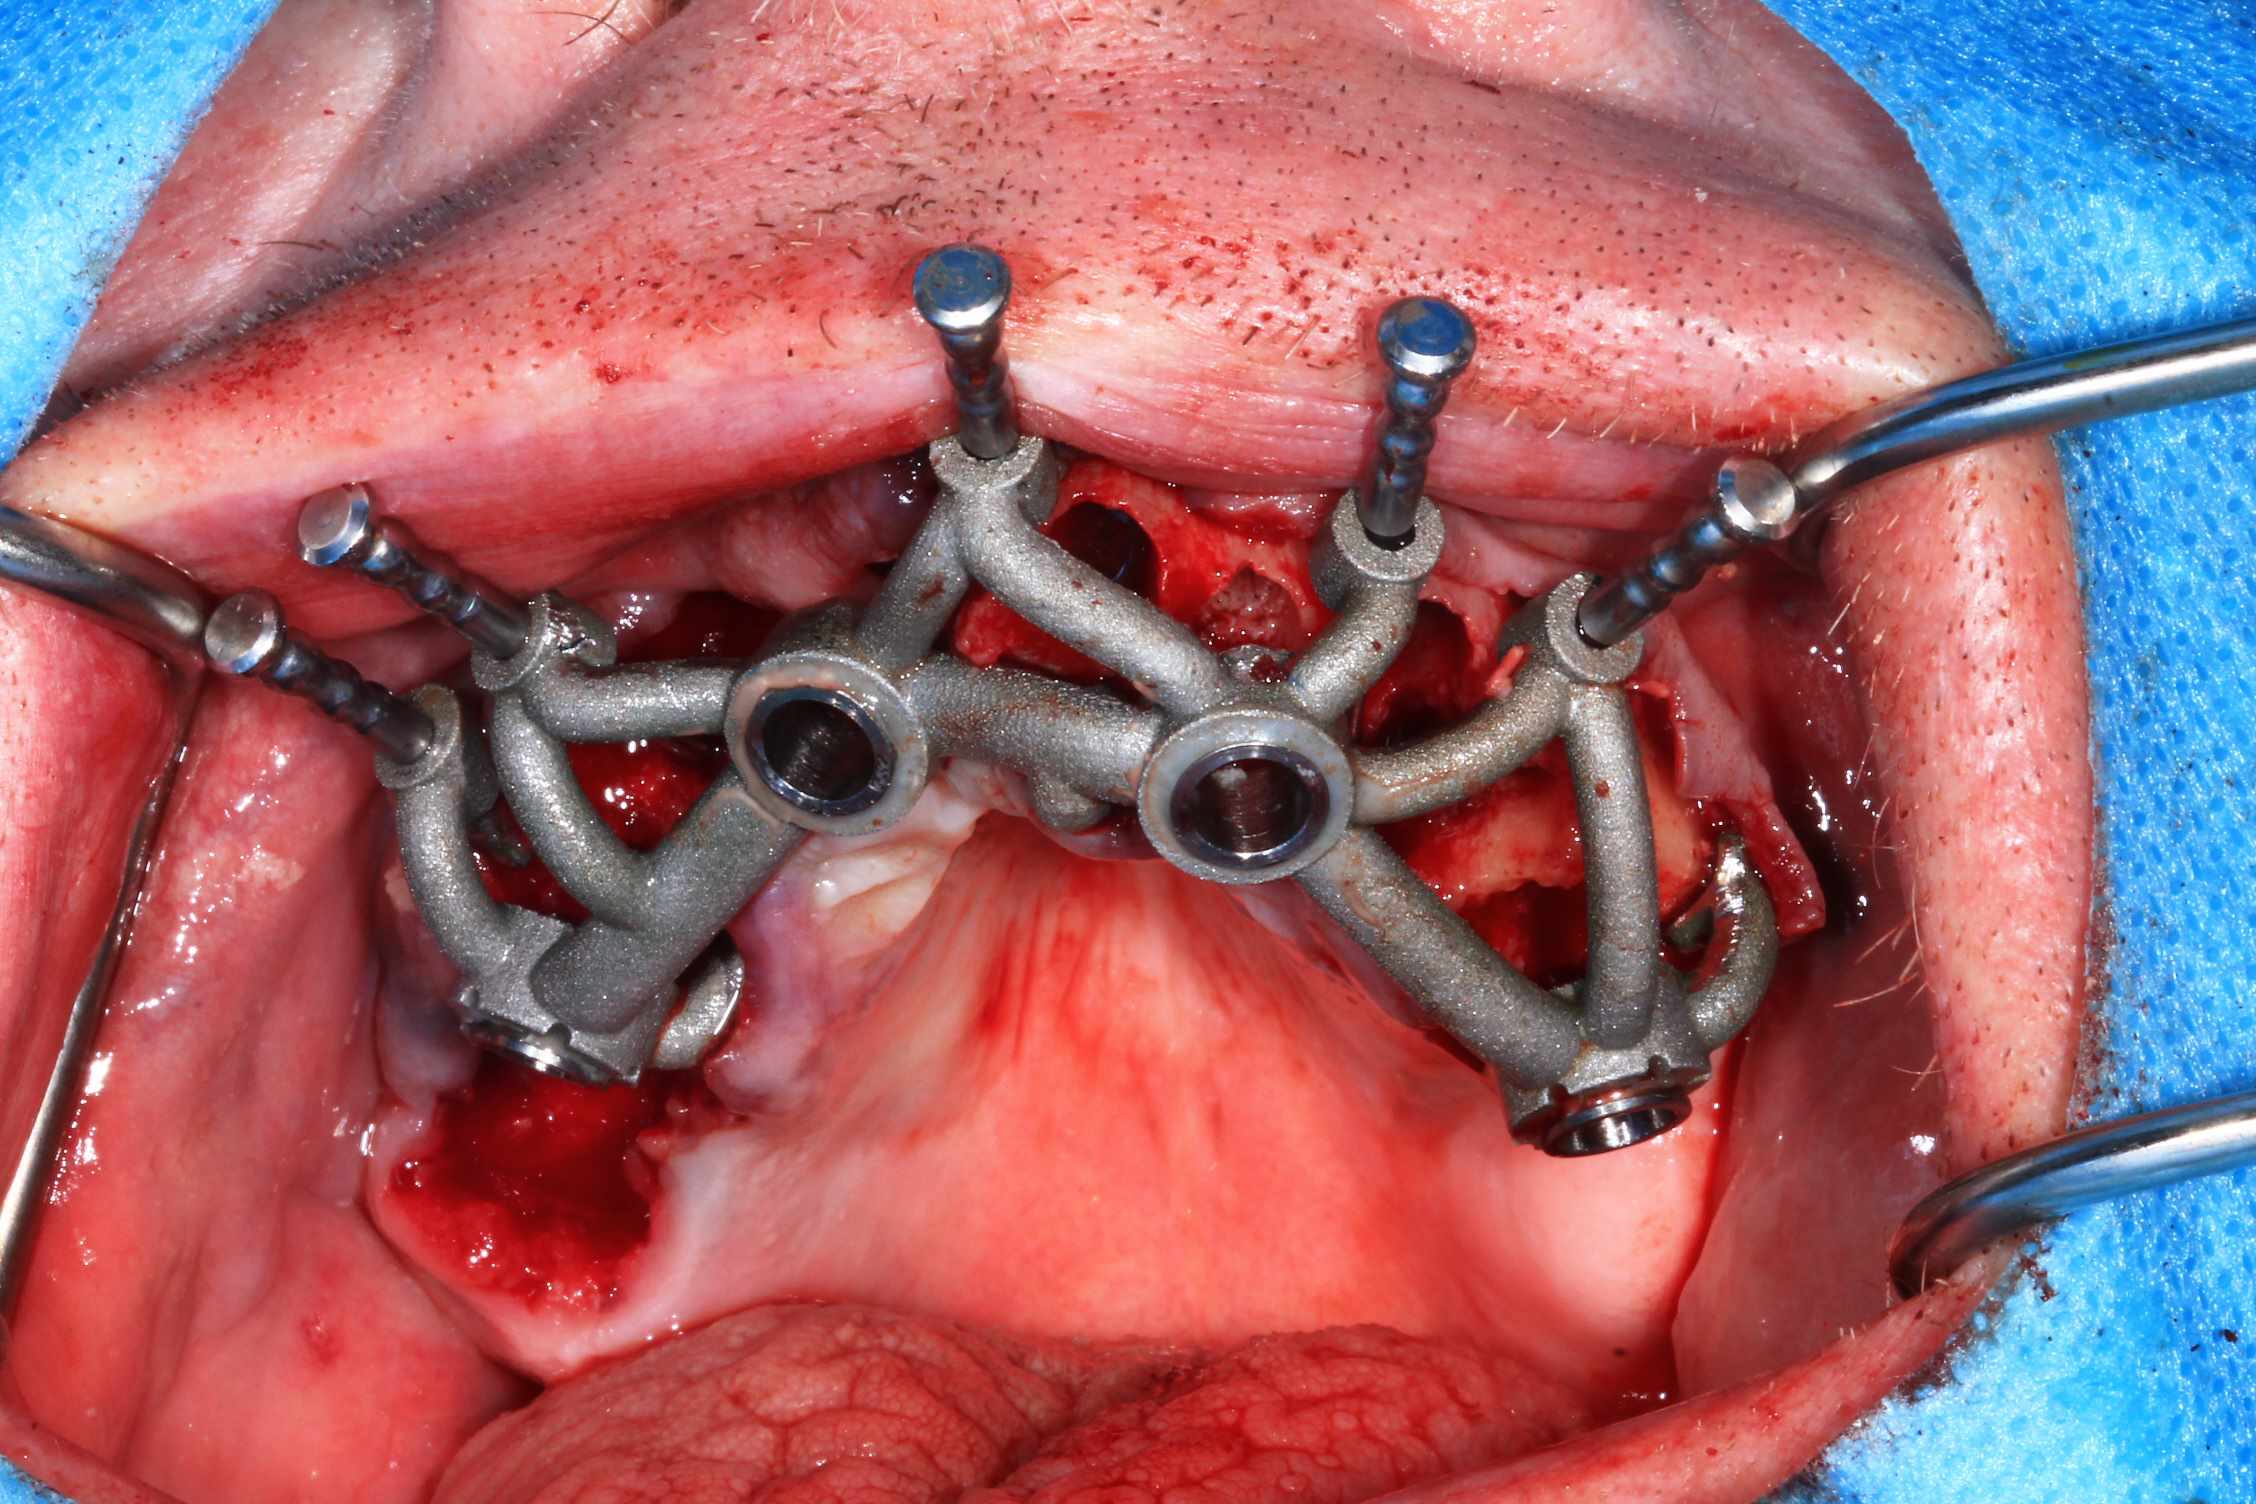

Cas 2 , suite : avec une saussage au passage..

le patient arrive a 9 h, Prise de sang, PRF, injection de corticoïde, anesthésie et installation au bloc. Premier coup de bistouri a 9h30. Dernière suture a 11h30.

K7lq3viye66rdgg66hkd26fcwcnj - Eugenol

Lwv6j6wyy3ynfk4una12he2dds3r - Eugenol

I7zqadqwo6ac3qraow6n3yxmuffa - Eugenol

Hu2y1wrw2x409z3kg6yu7t2vb36v - Eugenol

Mie6k3wjkz94let1xha2t8o56owm - Eugenol

Fwdzsncmbsahtduv8u1fn0t5tuzn - Eugenol